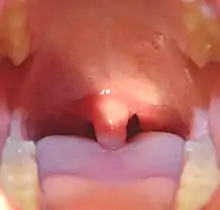

Mouth of a child showing the uvula and swollen tonsils

A child's swollen uvula with tonsils